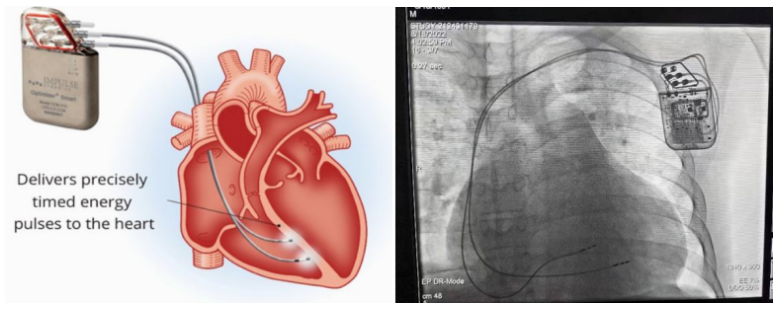

①植入式心臟復律除顫器

Implantable Cardioverter Defibrillator,ICD

植入式心臟復律除顫器是一種具有除顫功能的高級起搏器,是一種體積小、能植入患者胸部皮下組織的醫(yī)療設備。慢性心衰患者易發(fā)生室性心動過速或心室顫動,導致心源性猝死(SCD)。ICD 則能在幾秒內自動識別并治療快速室性心律失常,通過低能量心臟轉復和高能量除顫等功能,顯著降低惡性室性心律失常引起的猝死風險??杉皶r自動為患者轉復心律,通俗地說就是裝在體內的自動除顫儀。

國內研發(fā)企業(yè):無雙醫(yī)療、邁瑞、魚躍、久心、微創(chuàng)、維偉思、麥邦等